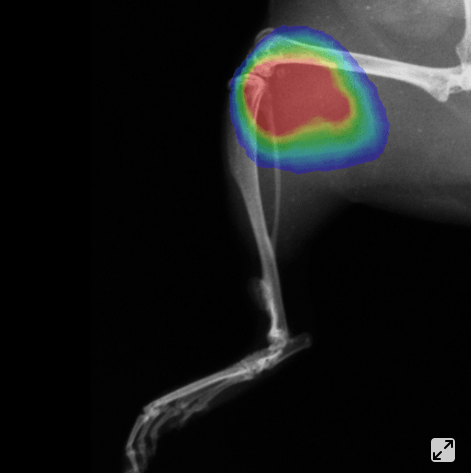

瑞孚迪(Revvity)全新一代小动物活体成像系统IVIS Lumina X5整合了最佳的高通量生物发光、荧光及高分辨率二维X光成像模块。扩展为五只小鼠的光学及X光大成像视野、独特的实验设置和样品标记辅助配件让研究人员能更便捷、更快速地获取疾病进展中解剖学和功能学各方面的稳定数据和答案。详言之,高分辨率X光图像与高质量光学图像数据的整合能力使其成为业界最顶 级的二维多模式活体成像系统。另外,IVIS Lumina X5包含先进的光谱分离功能,可通过高灵敏度多光谱成像来监测同一动物体内的多个生物学事件。

高分辨率、低辐射X光成像

生物发光、荧光及X光多模式成像